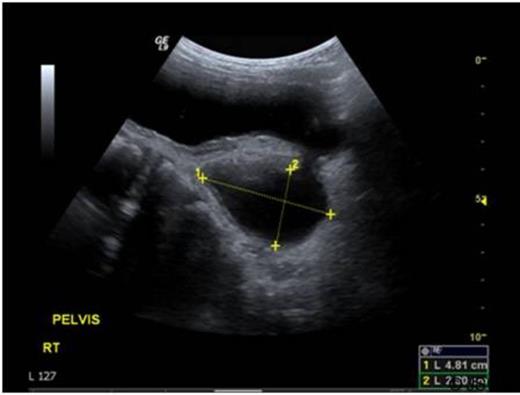

A previously well 2-year old boy presented with acute retention of urine requiring catheterisation. Renal tract ultrasonography revealed a large right-sided bladder diverticulum and a 2.2 x 1.3 x 3.6 cm lobulated thickening on the posterior bladder wall, which was associated with increased vascularity on Doppler imaging (Figure 1).

Ultrasound images demonstrating a posterior bladder wall lesion with increased vascularity